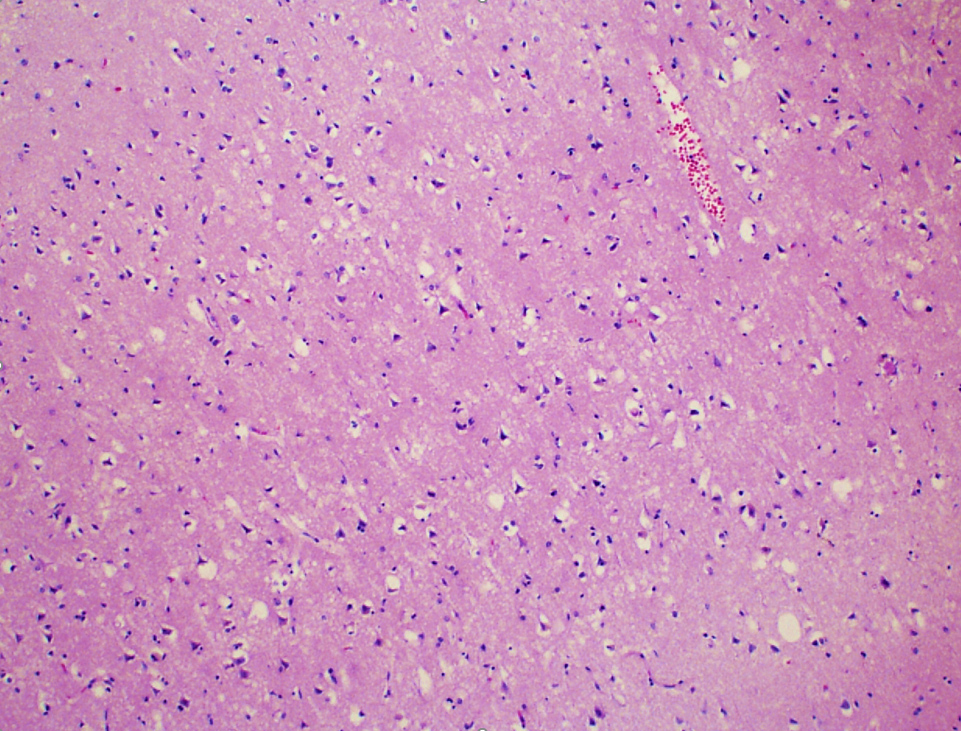

Microscopic (histologic) description

- Acute infarct (1 - 4 days) (Histopathology 2011;58:333)

- Neuronal changes: hypereosinophilic perikaryon (red dead neurons), cell body shrinkage, pyknosis (i.e., nuclear hyperchromasia), loss of demarcation of the nuclear features in later phases

- Neurons are more susceptible to ischemia than glia

- Neuropil vacuolation (i.e., tissue edema)

- May have some neutrophilic infiltrate

- Pannecrosis: all cell populations (i.e., neurons, glia, blood vessels) are necrotic; dead cells remain visible as hypereosinophilic structures that preserve the cell and nuclear outlines (pale neurons or "ghosts")

- Neuronal changes: hypereosinophilic perikaryon (red dead neurons), cell body shrinkage, pyknosis (i.e., nuclear hyperchromasia), loss of demarcation of the nuclear features in later phases

- Subacute (5 - 14 days)

- Dense macrophage infiltration and scattered siderophages

- Variable neutrophilic infiltration

- Peripheral reactive astrocytosis and microglial activation (i.e., rod shaped microglia)

- Hypereosinophilic neurons are still present in gray matter

- Neovascularization of necrotic tissue and reactive endothelial cells